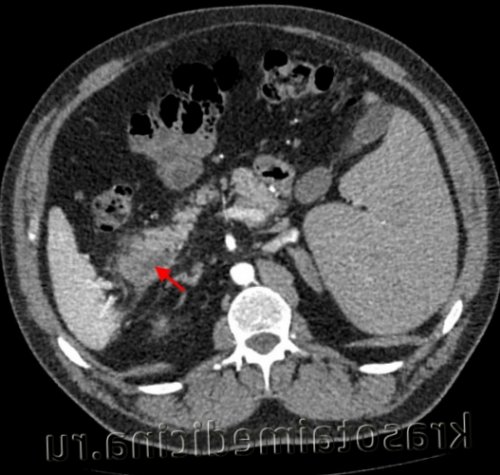

Муковисцидоз

• КТ (компьютерная томография) и МРТ (магнитно-резонансная томография) поджелудочной железы;Диагностика острого панкреатита• злоупотребление алкоголем;Панкреатит может быть инфекционного и неинфекционного происхождения. Вирусный панкреатит возникает вследствие инфекционного поражения поджелудочной железы, например, при кори, вирусном гепатите, туберкулезе.• вздутие живота, тяжесть;• тошнота и рвота, в рвотных массах иногда присутствует желчь;Острый панкреатит — это воспаление тканей поджелудочной железы, одним из главных признаков которого является острая боль в животе 1 . Это достаточно тяжелое заболевание, которое требует обращения к врачу и безотлагательного лечения.При тяжелой форме применяют октапептиды, селективно угнетающие панкреатическую секрецию, проводят интенсивную терапию для поддержания АД, стабилизации метаболических нарушений. Пациентам с установленной этиологией панкреатита показано лечение основного заболевания. При остром панкреонекрозе может выполняться некрэктомия поджелудочной железы, оментобурсостомия. При стойких болях, связанных с наличием кистозных образований, производится удаление ложных кист поджелудочной железы или марсупиализация истинных кист.• Обезболивающие препараты. Обычно используют ненаркотические анальгетики, которые при наличии спастических дискинезий дополняют миотропными спазмолитиками. При интенсивном болевом синдроме показана эпидуральная блокада, введение наркотиков.КТ органов брюшной полости. Панкреатит (в области хвоста поджелудочной железы) с наличием отека ее паренхимы, жидкостного содержимого вблизи ее края, на фоне утолщение фасции Героты слева• Исследование панкреатических ферментов в крови. Повышение уровня альфа-амилазы в 3-4 раза (при норме до 50 Ед/л) в первые сутки указывает на острый процесс или обострение хронического воспаления. С 4 суток проводят измерение уровня липазы — диагностически значимо двукратное увеличение показателя.Классическими симптомами острого панкреатита является триада Мондора — вздутие живота, сильная, внезапная боль, которая может привести к потере сознания, и многократная рвота, не приносящая облегчения. Кроме того, общее состояние пациента обычно быстро ухудшается с такими отличительными признаками, как тахикардия, снижение артериального давления, повышенная потливость и бледность кожи.• Особенности клинического течения. Хронический панкреатит бывает редко и часто рецидивирующим. При постоянном наличии симптоматики говорят о персистирующем течении заболевания.